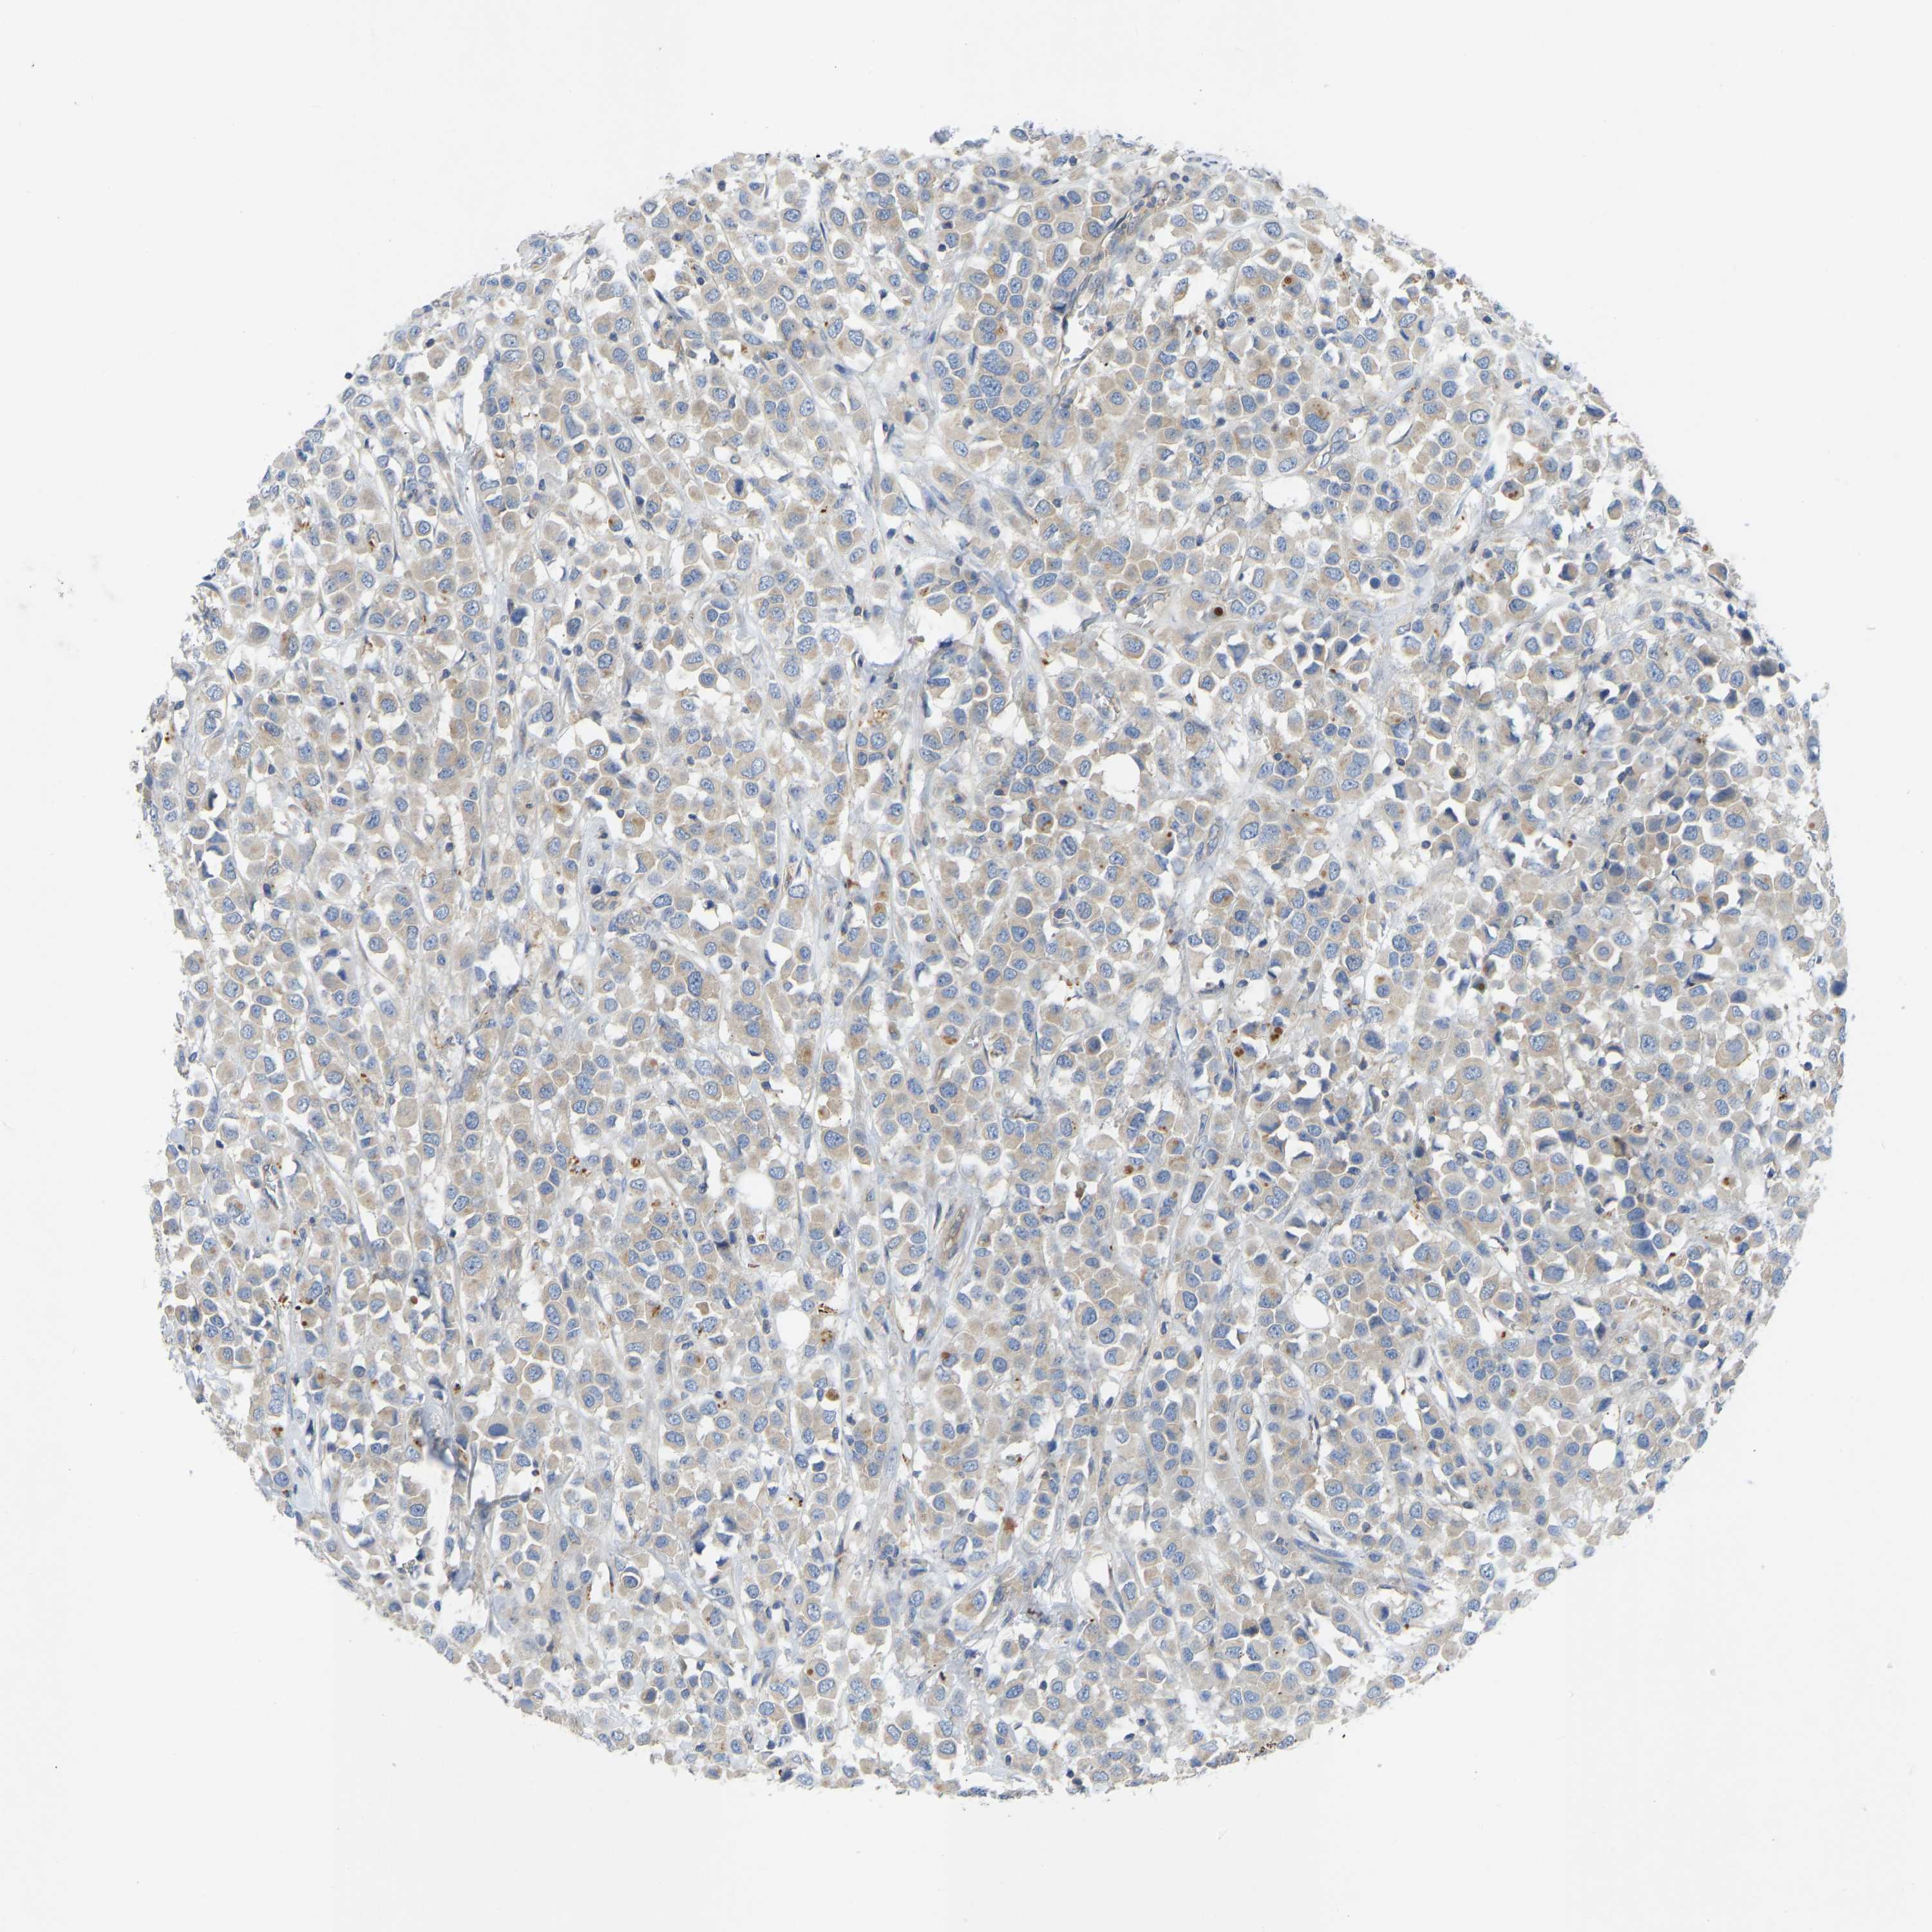

CANCER BREAST CANCER Show tissue menu

BRCA TCGA BRCA VALIDATION PROTEIN EXPRESSION

Breast cancer

Human cancer